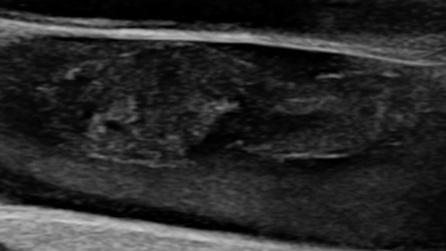

Неокклюзивный флотирующий тромбоз бедренной вены (УЗИ)